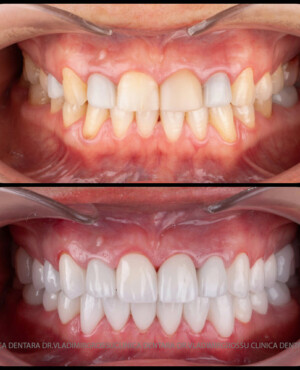

Cazuri clinice

Caz 1

Caz 2

Transformările estetice și impactul reabilitării asupra vieții pacienților

Reabilitarea dentară produce o schimbare vizibilă și profundă în aspectul pacientului, cu efecte pozitive evidente asupra stimei de sine și a calității vieții. Mulți pacienți relatează bucuria redobândirii funcției masticatorii și dispariția complexelor legate de aspectul dentar.